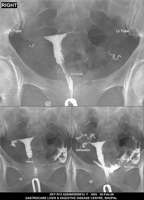

Section: HSG

Total: 49 Cases